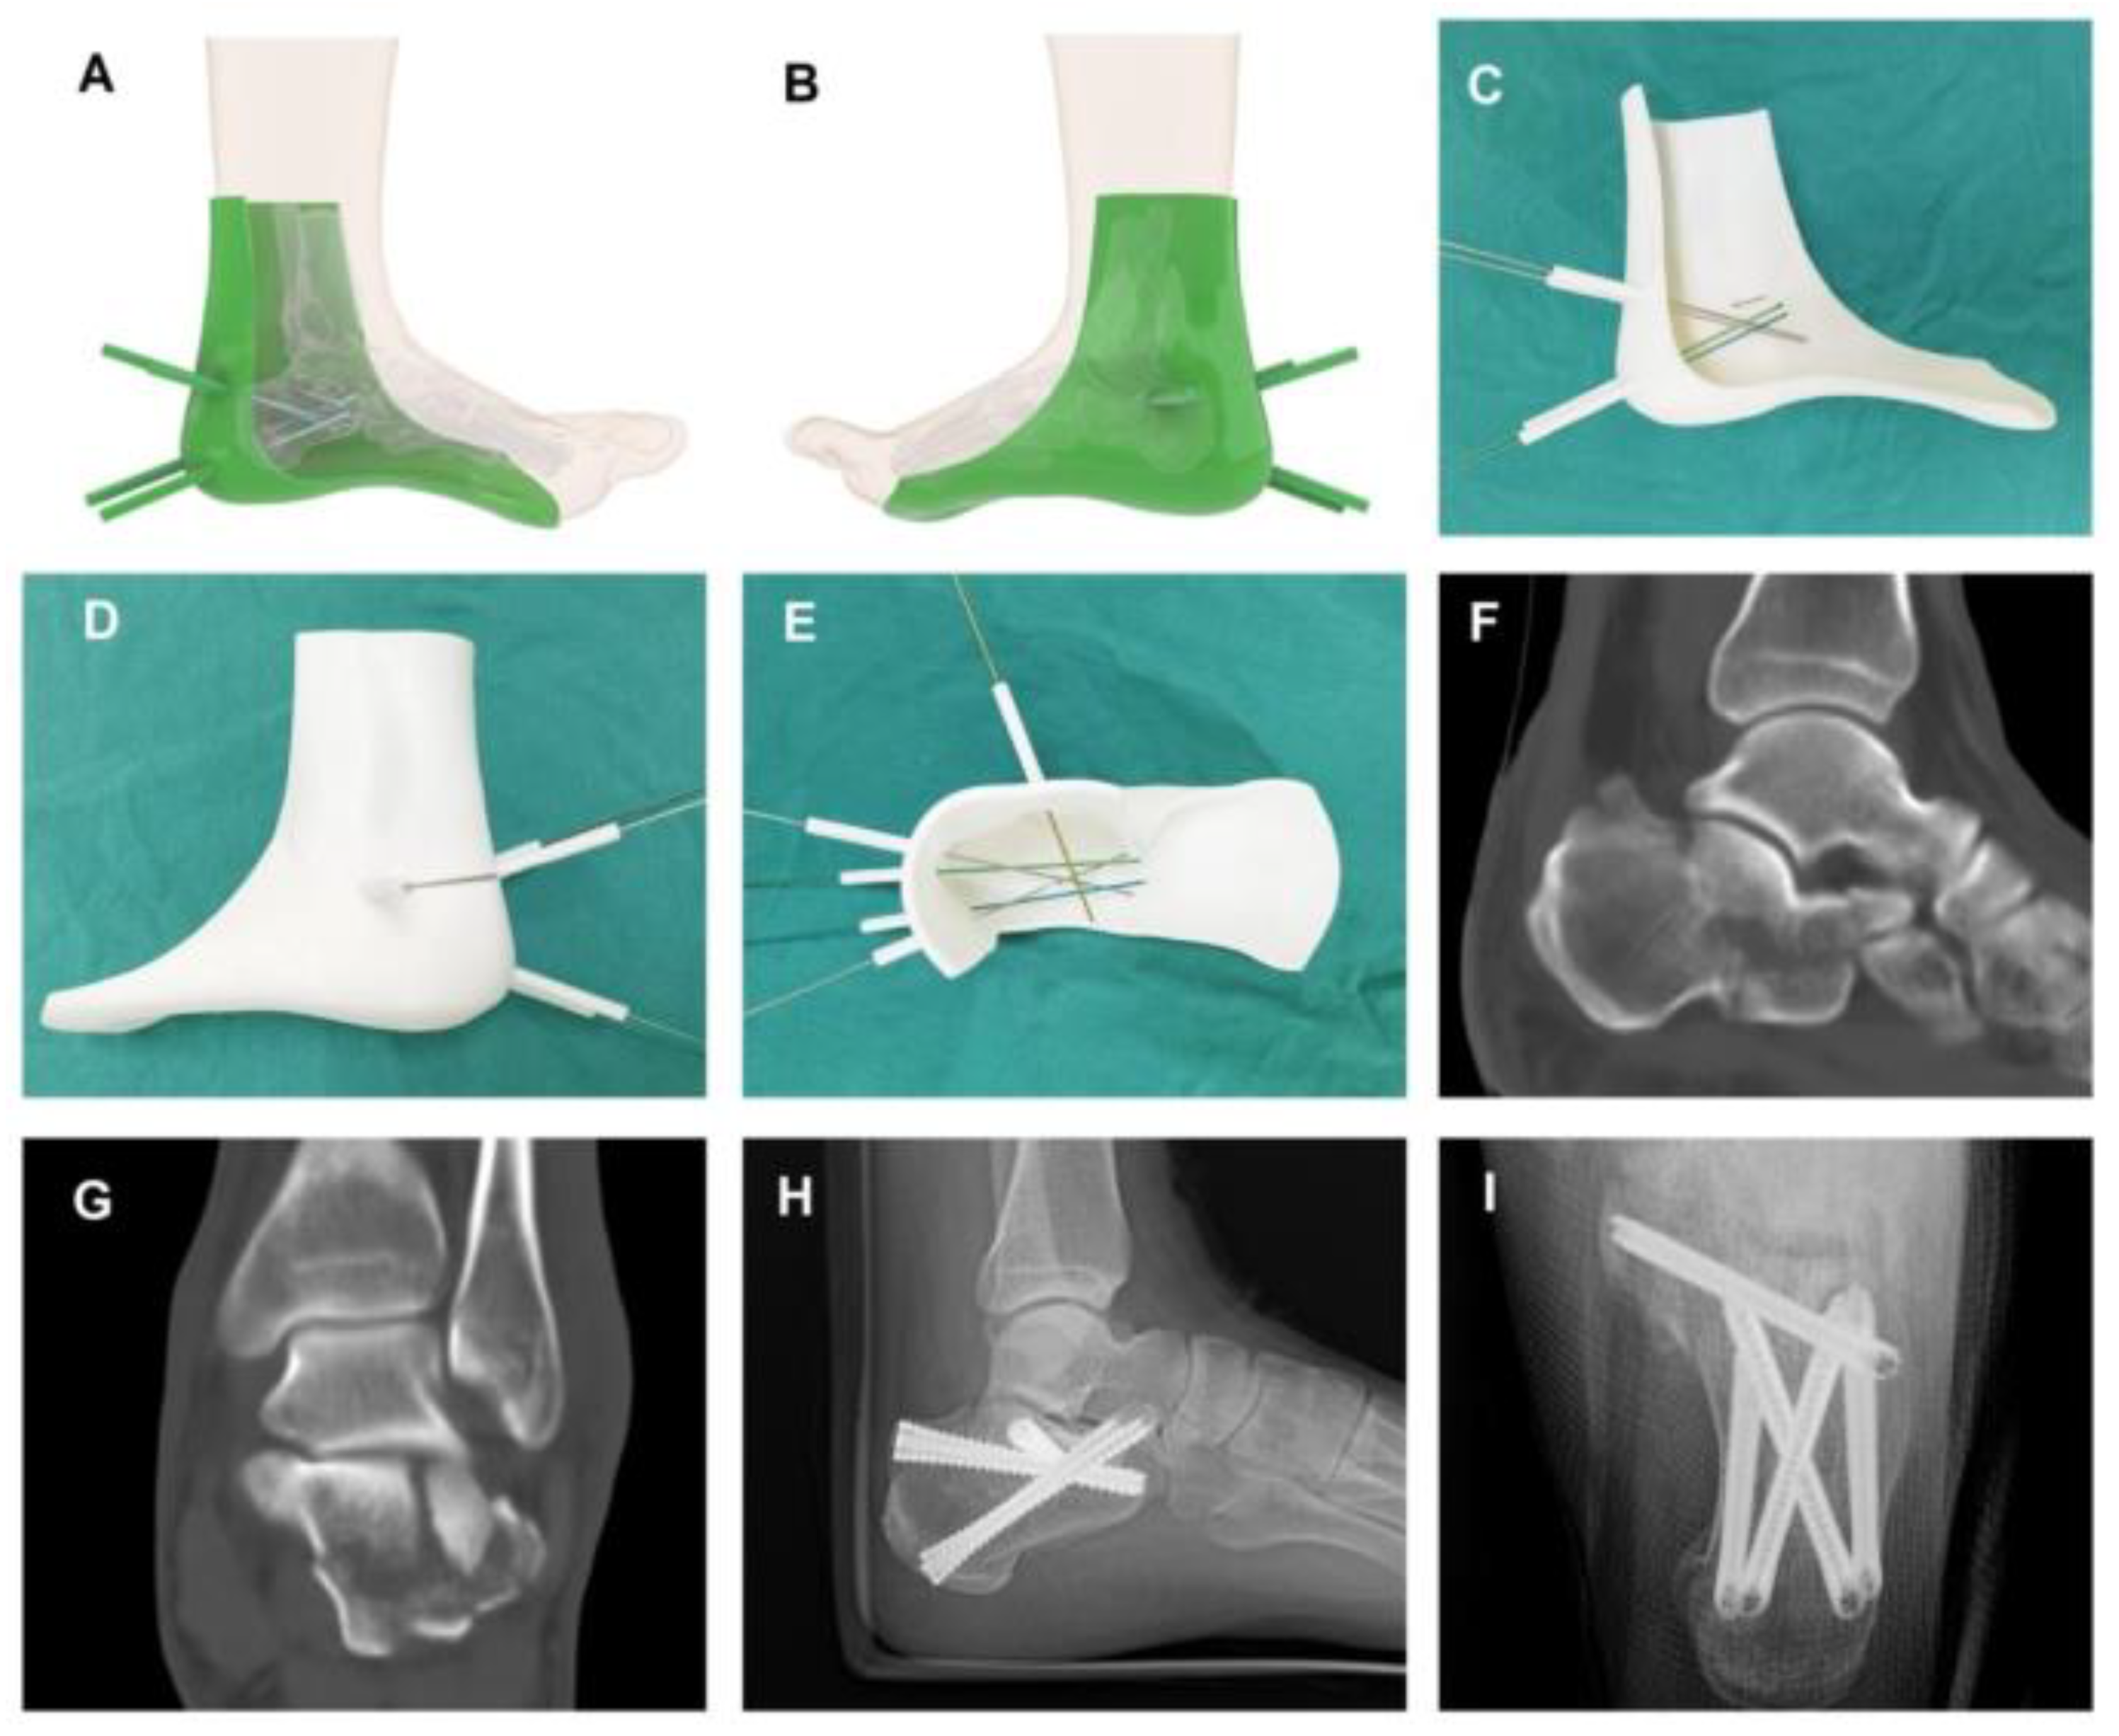

- Song, Q.; Li, T.; Xia, H.; Li, Y.; Feng, C.; Lin, Y.; Wang, H.; Hu, J.; Jiang, Q. Three-Dimensional Printed Cast Assisted Screw Fixation of Calcaneal Fractures: A Prospective Study. BMC Musculoskelet. Disord. 2023, 24, 802. [Google Scholar] [CrossRef]